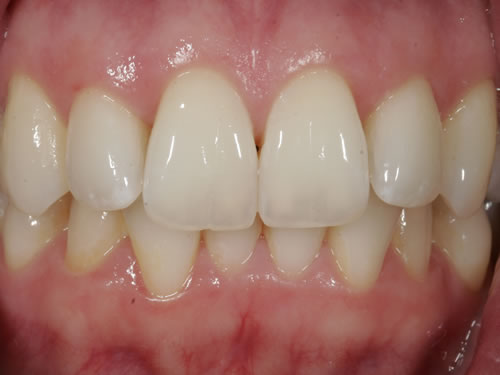

Eine besondere Herausforderung ist die Oberkieferfrontzahnregion. Der Wunsch nach einem perfekten Resultat ist geradezu selbstverständlich. Jeder möchte große, weiße Zähne und ein gesundes, reizloses Zahnfleisch besitzen (Abb. 3.30).

Abb. 3.30: Perfektes Resultat einer Versorgung.